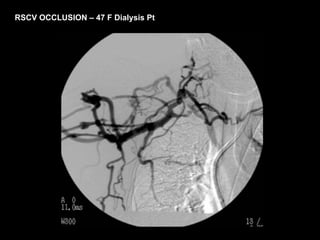

RSCV OCCLUSION –47 F Dialysis Pt